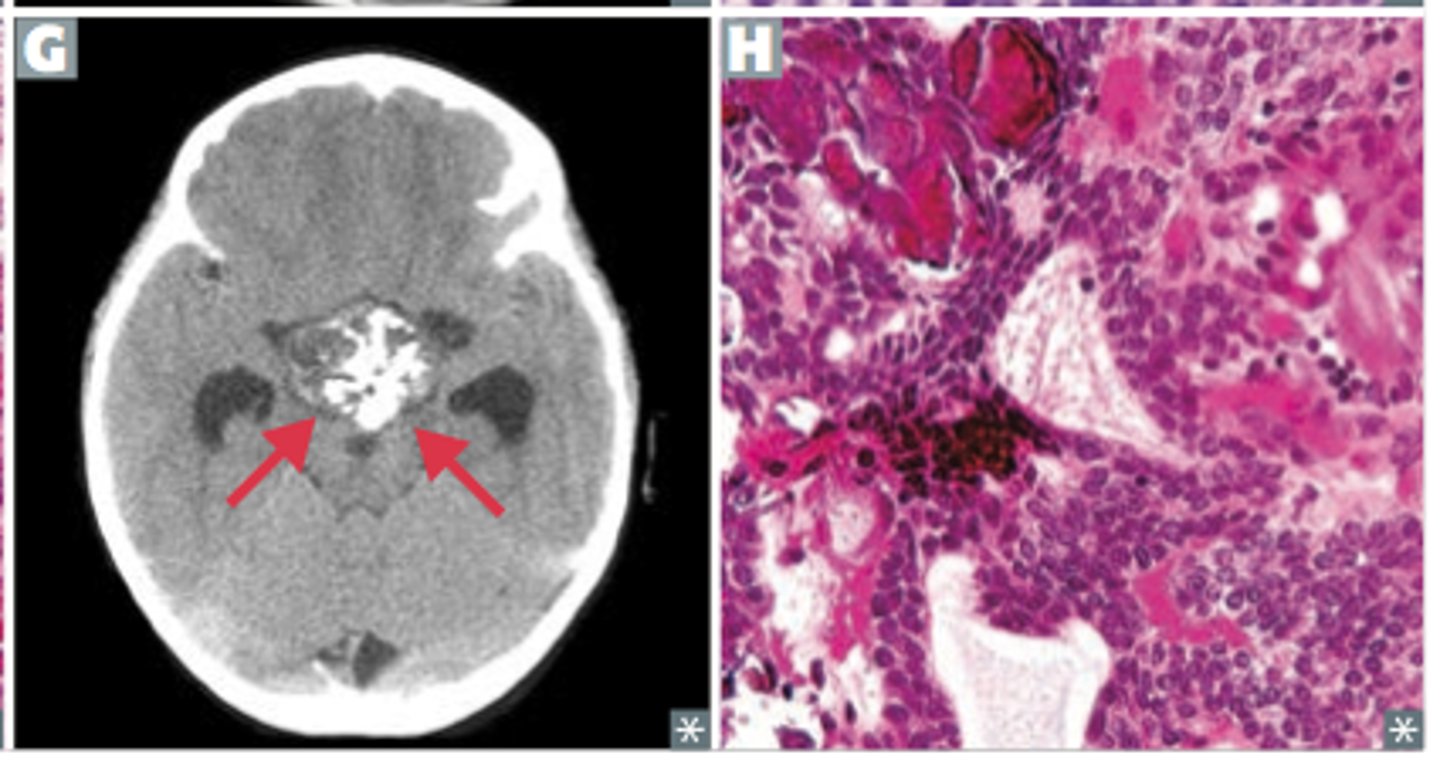

Craniopharyngioma

rare extra-axial epithelial tumor the sellar region

lobulated spongy mass that usually contains cystic spaces

gross pathology of Adamantinomatous craniopharyngioma

increased IICP, compression of optic chiasm, symptoms of hypopituitarism

Adamantinomatous CPHs typically have a lobulated contour as a result of usually being multiple cystic lesions. Papillary CPHs tend to be more spherical in outline

CT or MRI

imaging of choice for CPHs